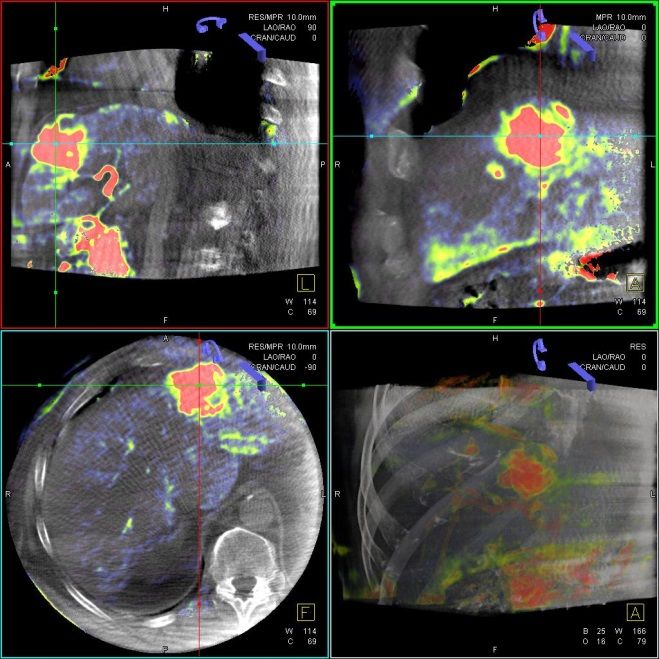

Die Selektive Interne Radiotherapie (SIRT) wird in der Fachliteratur auch Radioembolisation (RE) genannt. Hierbei werden gezielt kleine, radioaktive Kügelchen, sog. Mikrosphären, über den Katheter (siehe TACE) von mehreren Positionen in der Leber mit dem Blutstrom in das gut durchblutete Tumorgewebe gebracht und bleiben dort in den kleinen Gefäßen "stecken", die den Tumor ernähren. Von dort bestrahlt das in den Kügelchen enthaltene radioaktive Element Yttrium-90 über mehrere Tage hinweg das Tumorgewebe und zerstört es selektiv. Dieses Verfahren kann bei Leberkrebs oder -metastasen eingesetzt werden, wenn die Herde trotz Chemotherapie weiter wachsen und nicht chirurgisch oder mittels RFA und TACE behandelbar sind.

Das Verfahren wird von der interventionellen Radiologie zusammen mit der Partnerabteilung der Nuklearmedizin sowie den entsprechenden Partnerkliniken geplant und durchgeführt.

Abbildung Körper: Schematische Darstellung des Zugangsweges bei SIRT-Therapie über die Leistenarterie. Die arteriellen tumorversorgenden Gefäße in der Leber werden selektiv dargestellt und von dort wird die Therapie lokal appliziert. (Bildrechte beim Thieme-Verlag!)